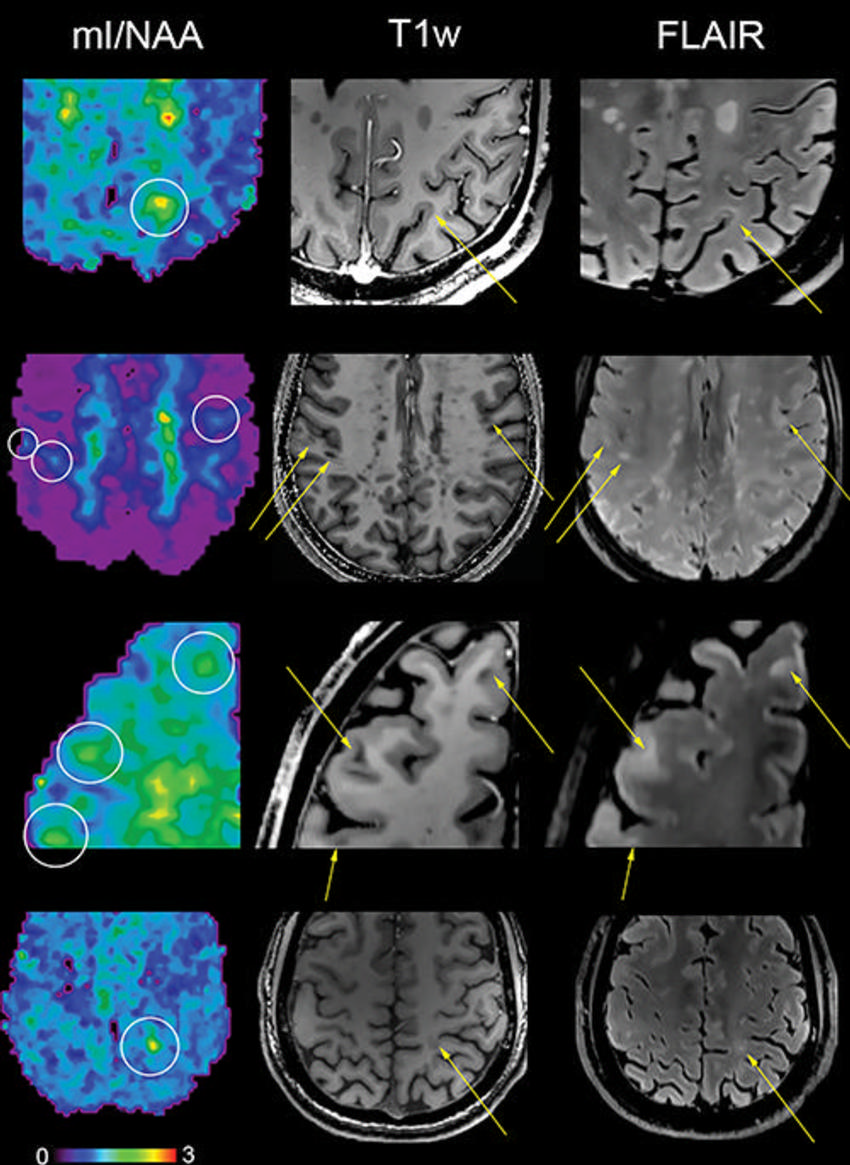

Figure 3. Metabolic maps showing the ratio of myo-inositol to N-acetylaspartate (mI/NAA) clearly depict small subcortical or juxtacortical lesions (circles) that appear inconspicuous at T1-weighted MRI (T1w)/fluid-attenuated inversion-recovery (FLAIR) imaging (indicated with arrows in three participants with multiple sclerosis).